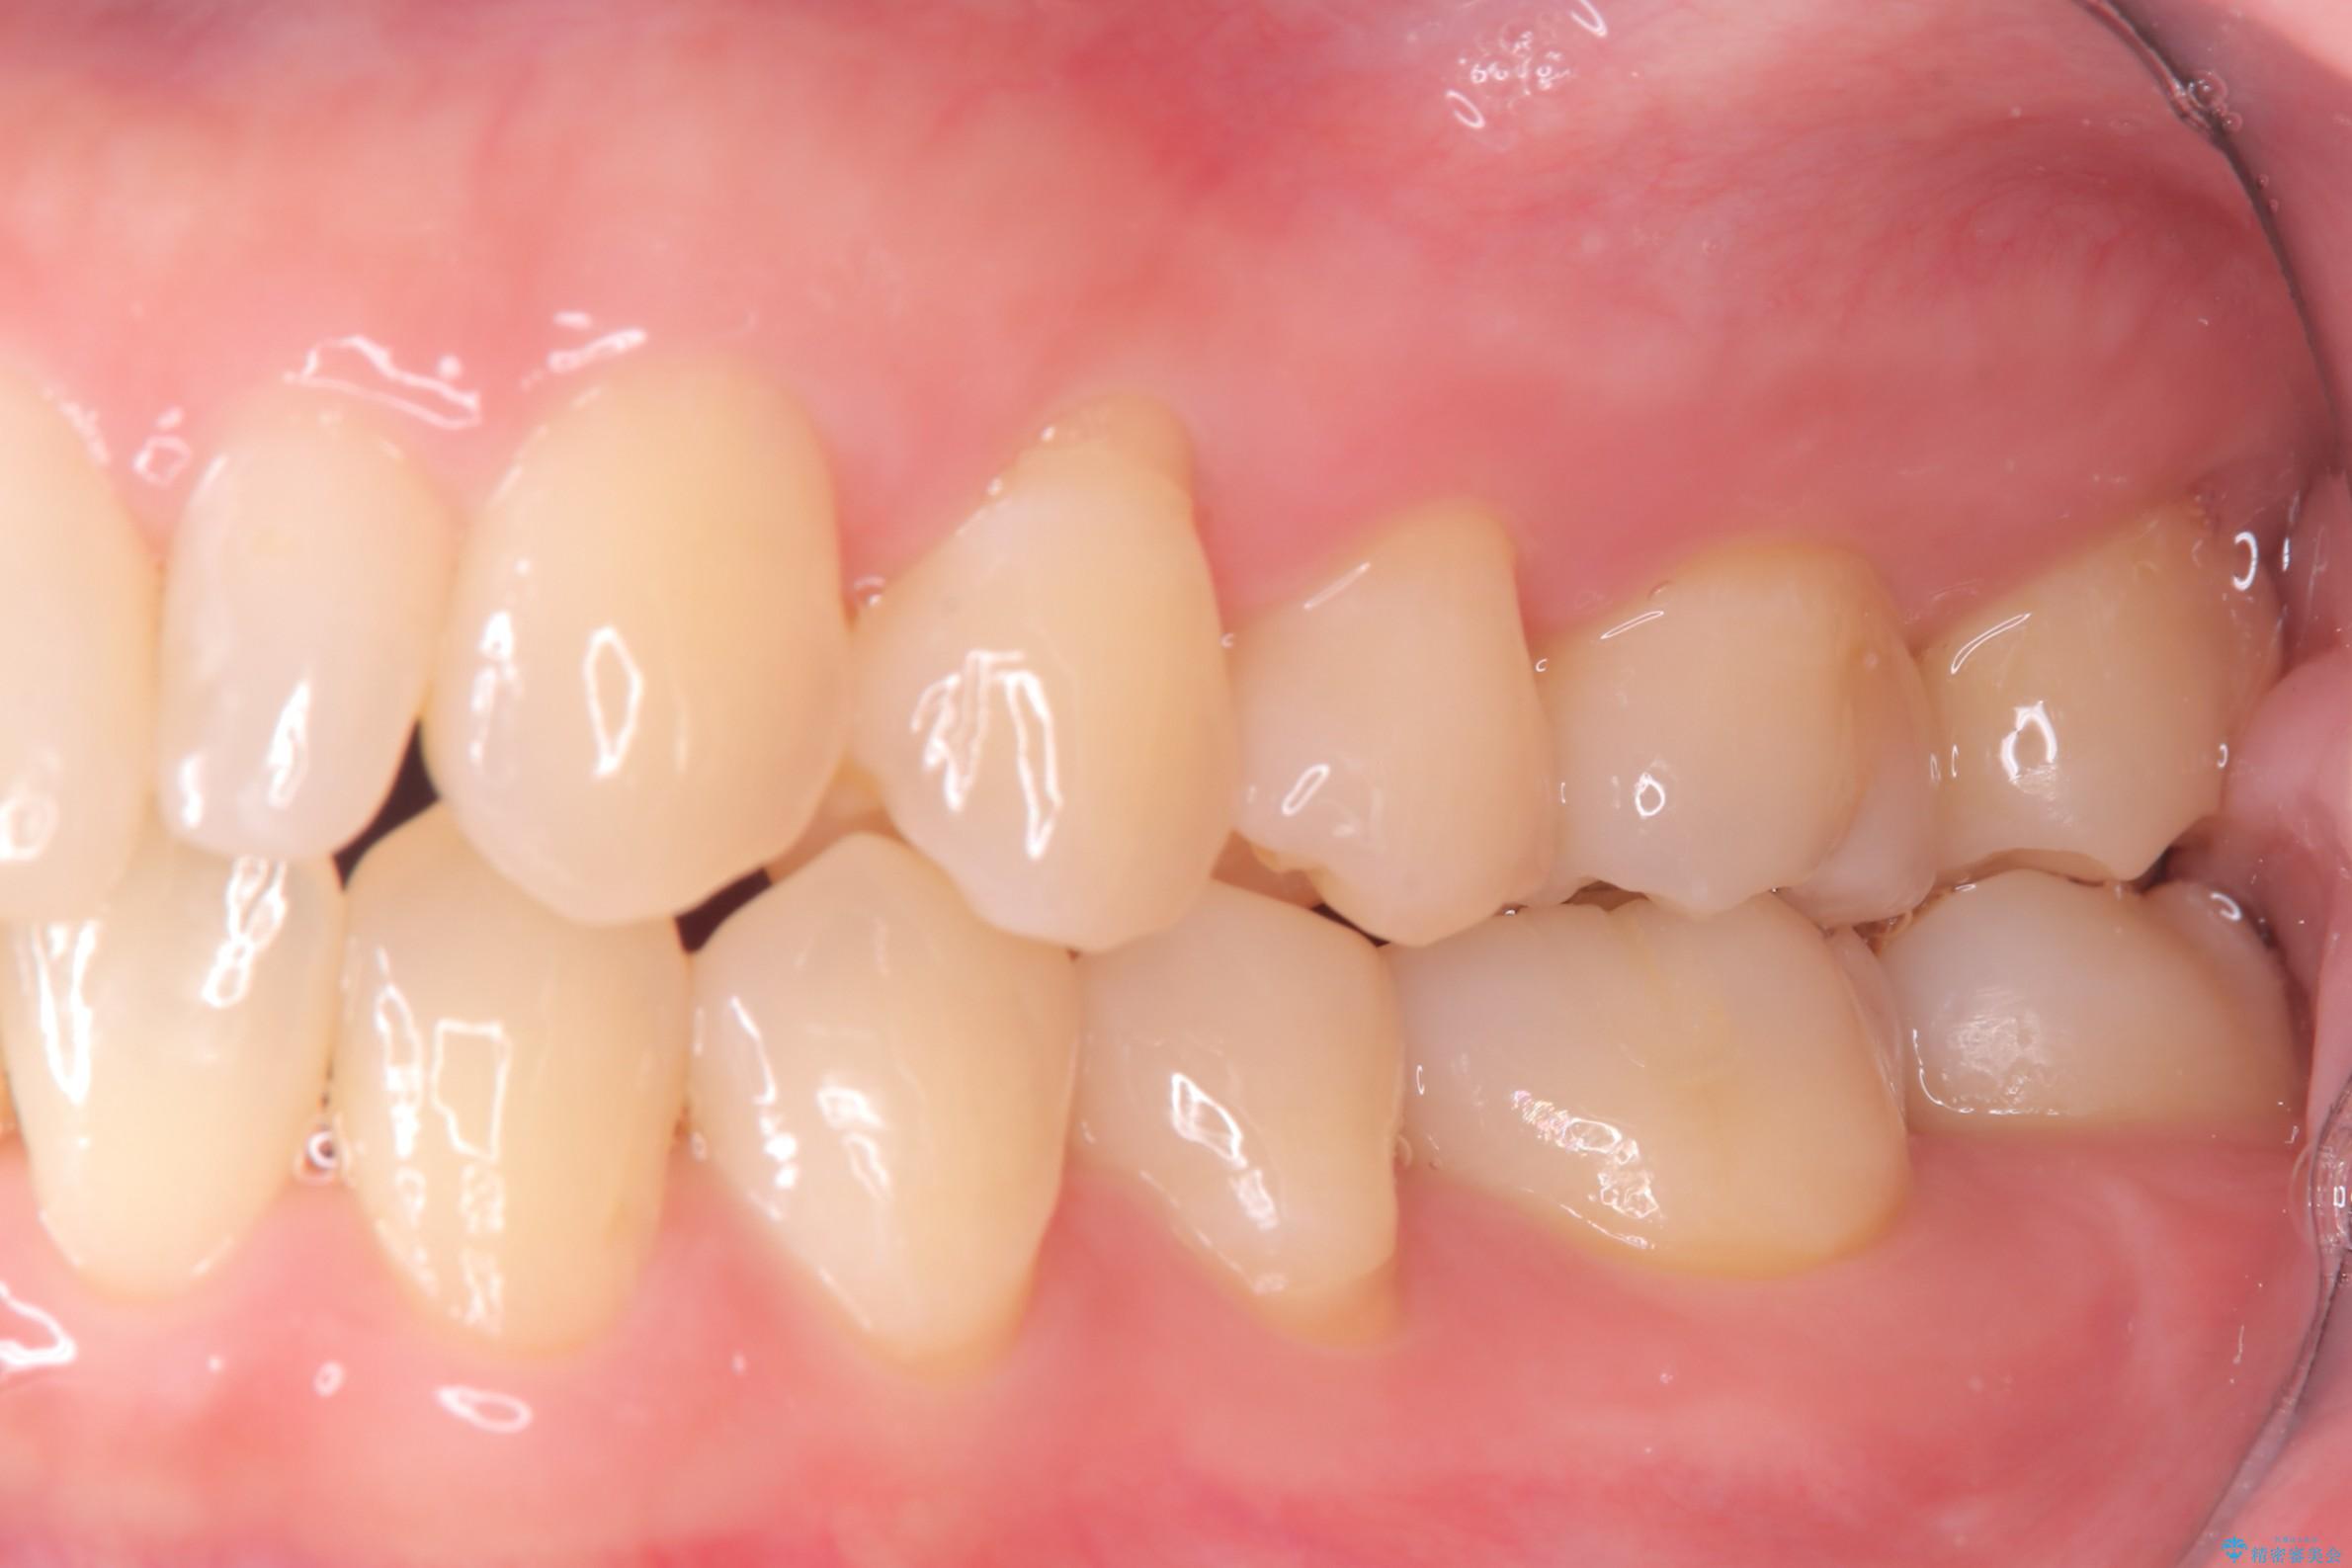

今回は、経年的な劣化が少なく、汚れが付着しにくいセラミックインレーを用いて治療を行いました。

セラミックインレー装着時には、唾液が入らないようラバーダムシートを使用し、接着精度を高めることで、長く安心して使っていただける治療を心がけています。